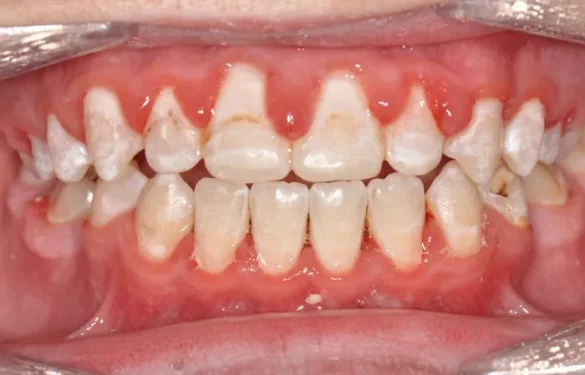

Can You Get Braces with Cavities?

In the world of orthodontics, the question of whether braces can be worn is a common concern for patients. The relationship between tooth decay and braces is not always straightforward and involves all aspects of oral health, from the structural integrity of the teeth, to the potential for bacterial growth and infection, to the smooth progression of orthodontic treatment and the ultimate achievement of corrective results.